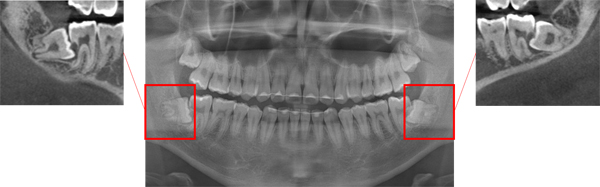

사랑니는 보통 10대 후반에서 20대 초반에 구강 내에서 가장 늦게 맹출(치아가 기능하는 정상적인 위치까지 이동하는 것)한다. 사랑니는 맹출 공간이 부족하고 최후방에 위치하기 때문에 바르게 자라나지 못하는 경우가 많다.

또한 증상이 없으면 존재 자체를 모르는 경우가 많은데 비스듬하거나 수평 방향으로 맹출해 인접치의 치아 우식이나 치주염 등을 일으키기도 한다.

매복된 사랑니 중에서는 낭종이나 양성 종양과 연관된 경우도 있어 예방적인 차원에서 제거를 고려한다.